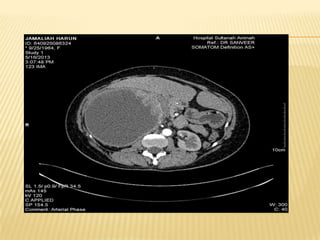

CT LIVER

IMAGING  Usg HBS Huge heterogenous cystic mass in the right liver lobe measuring > 20.5cm X 12cm.Presence of gallstone in GB.IHD and CBD not dilated Imp : suggestive of hydatid cyst with diffrential of amoebic liver abcess *** further history : h/o of multiple visits to egypt within past few years. Last visit was in feb 2013 whr she took local salad dish with grilled fish and snails delicacies